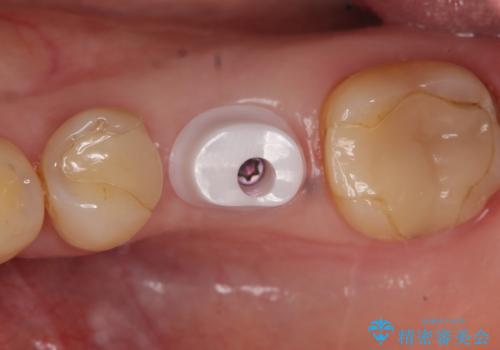

カスタムアバットメントについて

カスタムアバットメントは患者様それぞれの歯茎に合わせて製作されたオーダーメイドのアバットメントです。

既製のアバットメントに比べ適合がよく、高い清掃性を誇ります。